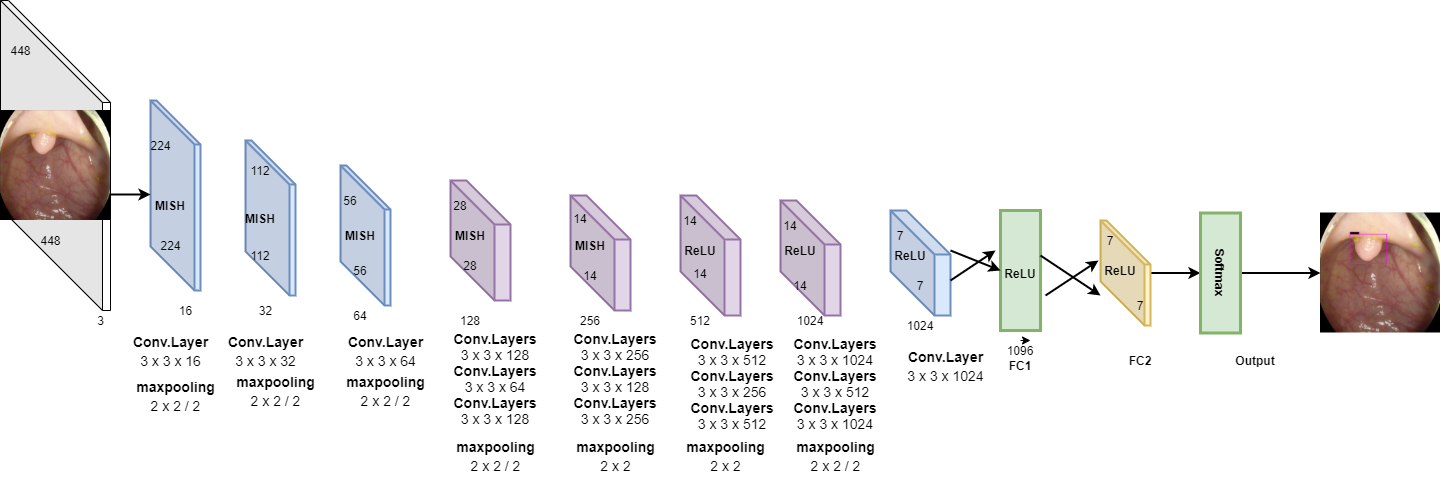

Fig. 1 shows the general flow of the proposed approach for polyp detection in colonoscopy images. As shown in Fig. 2, the proposed deep CNN consists of 16 convolutional layers, two fully connected layers, and a softmax layer. To lessen computational complexity and improve hierarchical image features, maxpooling is used for the first 15 convolutional layers. For better image feature extraction, different sizes of convolution kernels are employed, with a stride of 2. In the proposed model, we have implemented Mish [21], which is a self-regularized smooth non-monotonic activation function, in the first 15 convolutional layers. This implementation was done after extensive trials to find the best matching position of the activation function. As observed in Fig. 3, Mish is an unbounded above result in avoiding saturation due to capping. This may normally lead to slow training, i.e., near-zero gradients. A better gradient flow and smooth propagation of information across deeper layers are achieved by the infinite order of continuity and a small allowance of negative values, in comparison to a strictly bounded rectified linear unit (ReLU) as an activation function. MISH can be expressed mathematically as:

In the last layers, ReLU is used as an activation function to reduce the likelihood of gradient vanishing and achieve the sparsity. Flattening is done by two fully connected layers to yield a single continuous linear vector followed by softmax or the regression layer to generate the required output. The approach of using Mish and ReLU as an activation function results in smooth propagation of information across deeper layers. MISH helps to avoid capping, and ReLU prevents the gradient from vanishing.

where is the learning rate of the , is the momentum indicating the previously updated weight contribution in the current iteration, and represent the scheduling rate which after each epoch decreases the learning rate . The simulation parameters used for the proposed deep CNN are given in Table. 1.